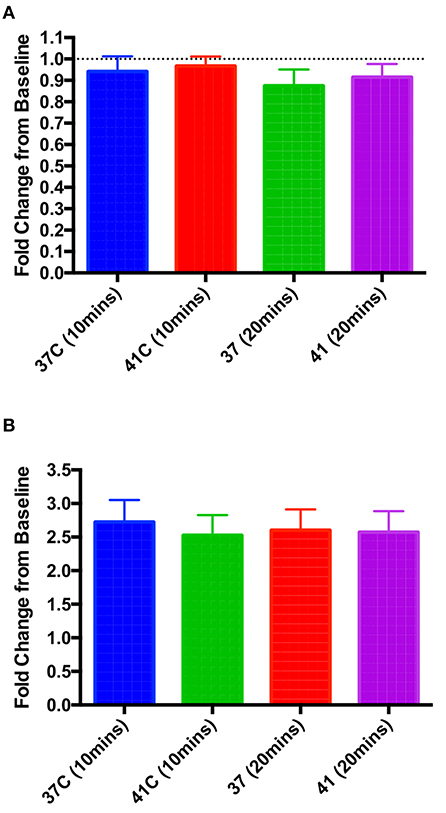

In vitro hyperthermia had no effect on baseline contractility or beta adrenoceptor responsiveness

Isolated rat left ventricular cardiomyocytes were perfused with Krebs-Henseleit (KH) solution at 37°C for 10 min, after which a measurement of cellular shortening was taken and perfusion temperature increased to either 41°C or maintained at 37°C (control). No significant changes in contractility were seen with this increase in temperature (Figure 5A). In a separate set of experiments, isolated cardiomyocytes were perfused with KH at either 37°C or 41°C, and after a 10 min stabilization period, a baseline measurement of cellular shortening was taken and isoproterenol (10−6 M) was added to the perfusate. Measurements were taken at 10 and 20 min post-isoproterenol addition, and no significant differences were seen between the two temperature groups at either time point (Figure 5B).

Figure 5. In vitro hyperthermia had no significant effect on either baseline contractility at 10 or 20 min post-temperature change (A) or the increase in contractility when 10−6 M isoproterenol was applied at either 10 or 20 min post-isoproterenol (B). One-way ANOVA, n = 9 and 10 cells (A), 8 and 7 (B), 37 and 41°C, respectively.